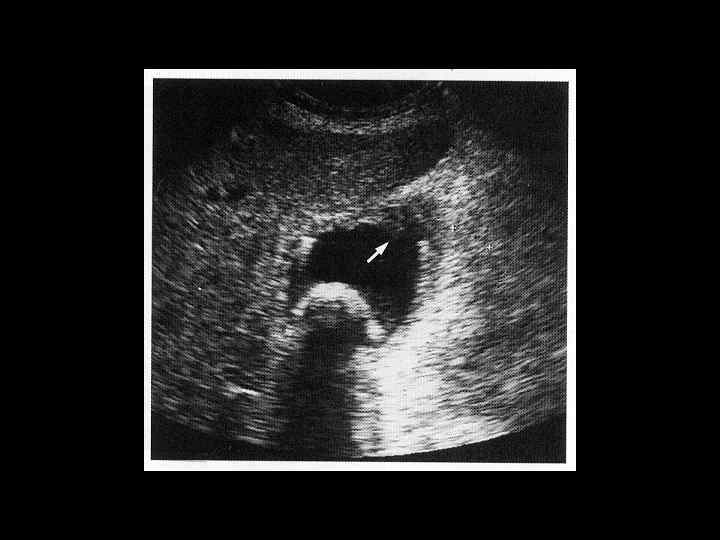

АКТУАЛЬНЫЕ ВОПРОСЫ РЕНТГЕНОЛОГИИ ЛУЧЕВАЯ ДИАГНОСТИКА ЗАБОЛЕВАНИЙ ЖЕЛЧЕВЫДЕЛИТЕЛЬНОЙ СИСТЕМЫ Желчекаменная болезнь УЗ семиотика